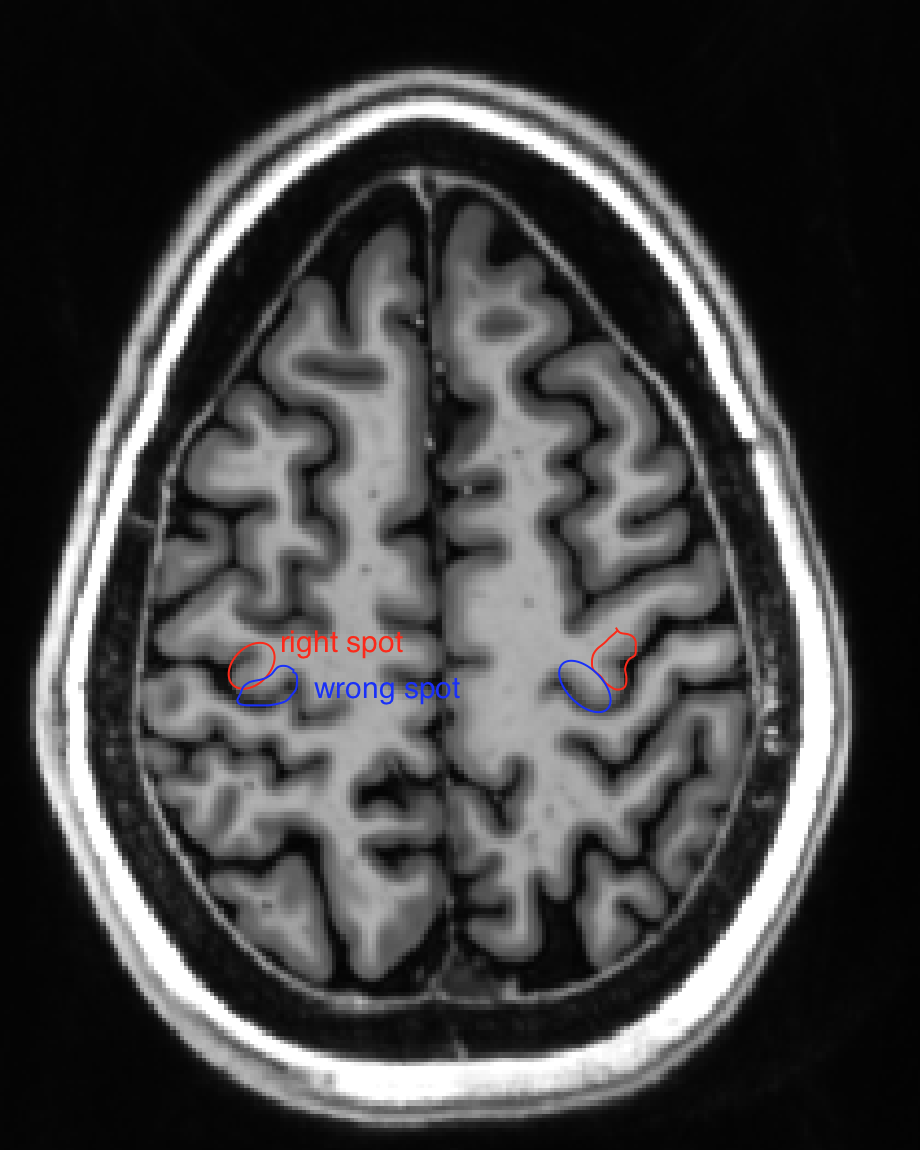

Screenshot 2018-03-20 09.54.08 renzohuber March 20, 2018March 20, 2018 Published by renzohuber View all posts by renzohuber Published March 20, 2018March 20, 2018